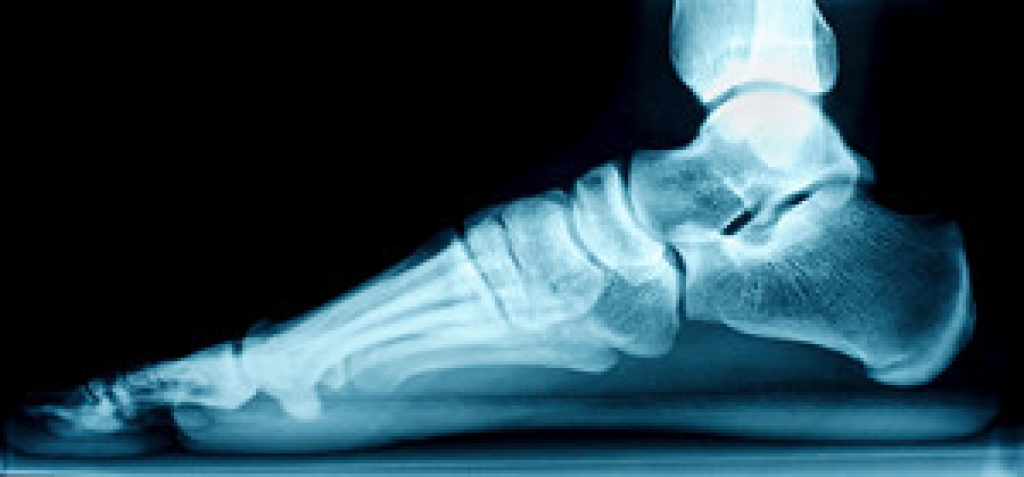

Achilles tendon – Stretching the foot out flat on the floor will relax the calf muscles and tendon. These exercises can be performed almost anywhere. Make sure you add these exercises to your daily regimen.